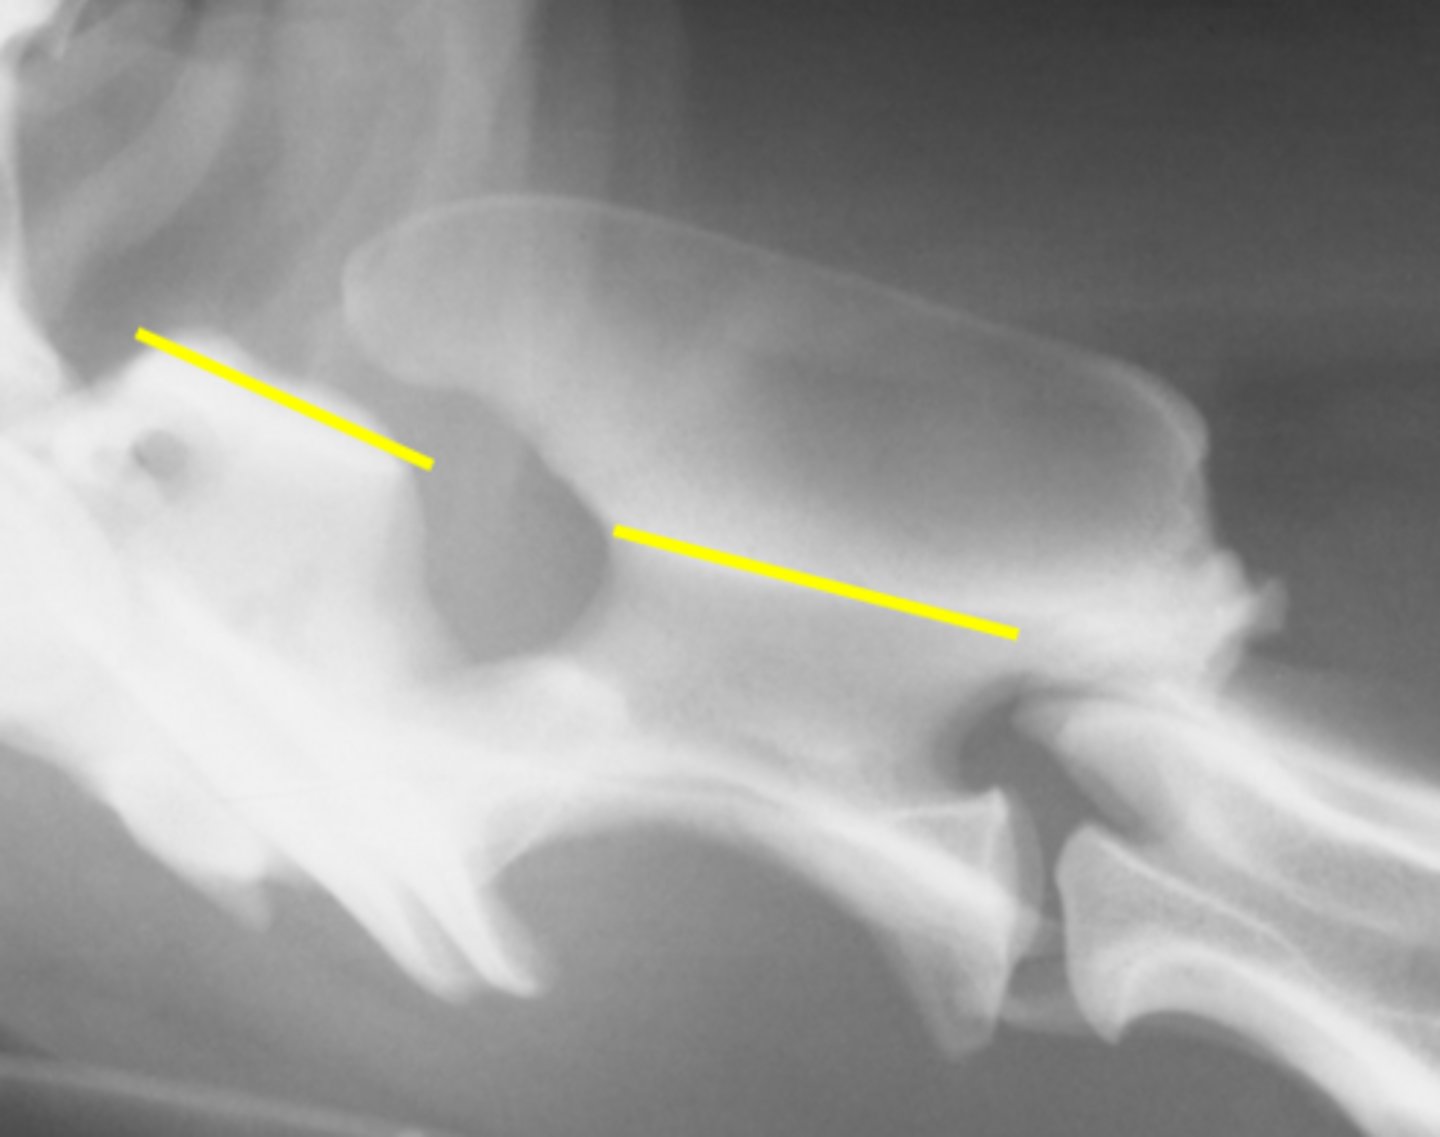

T/F: The dorsal arch of C2 should overlap C1

True

Which vertebra has a large, ventrally oriented transverse process?

C6

What is the anticlinal vertebrae?

T10/11

T/F: The disc space between T10/11 is often wider

False, narrower

Which vertebrae are often shorter to the adjacent ones?

C7 and L7

Which vertebrae have indistinct ventral borders due to the diaphragm?

L3 and L4

Which intervertebral foramina look like a horse head?

Lumbar

Which disc space is often wider compared to others?

L7 - S1

What is the first vertebrae will have dorsal spinous processes that superimpose over the intervertebral space?

T1 (C7 is more central)